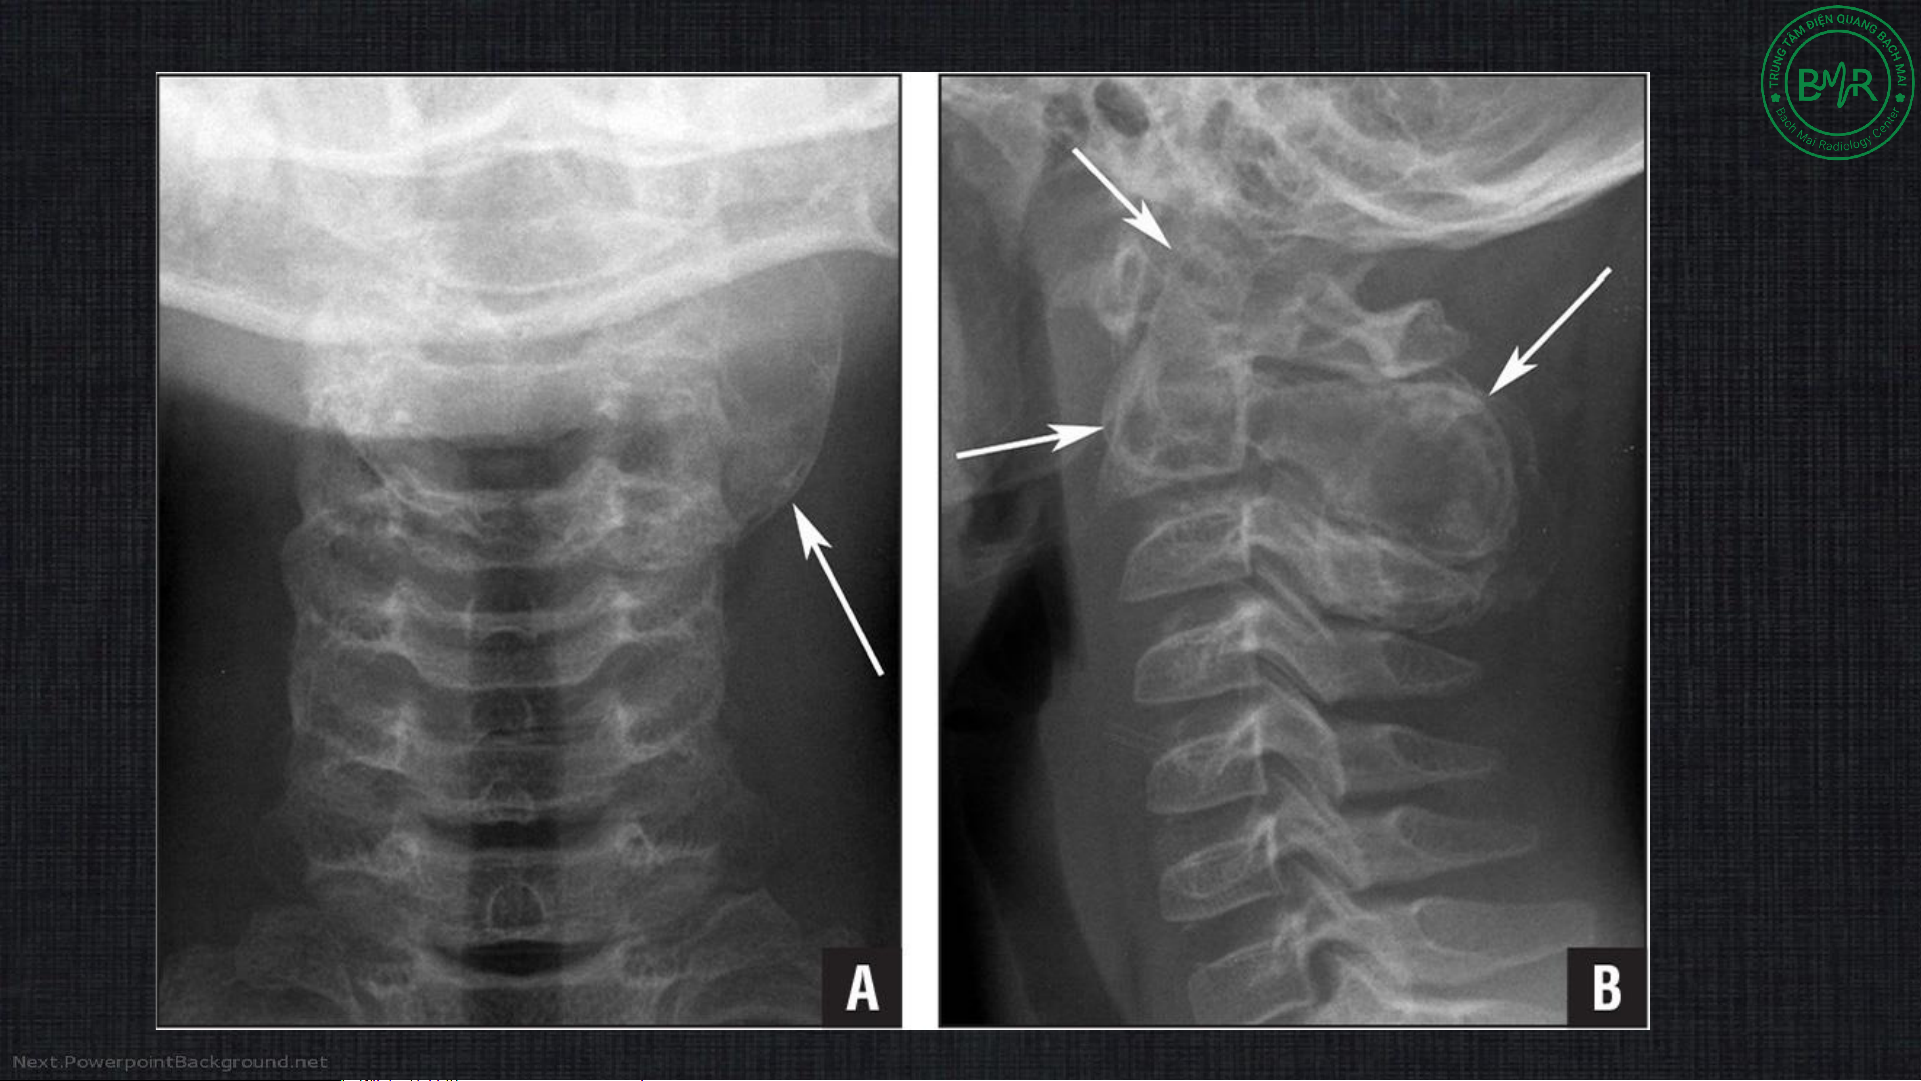

Ponticulus posticus (bất thường Kimmerle) •

Hình thành cầu xương nhỏ phía

sau do vôi hóa màng chẩm – đội •

Hẹp đoạn V3 ĐM đốt sống khi đi qua C1